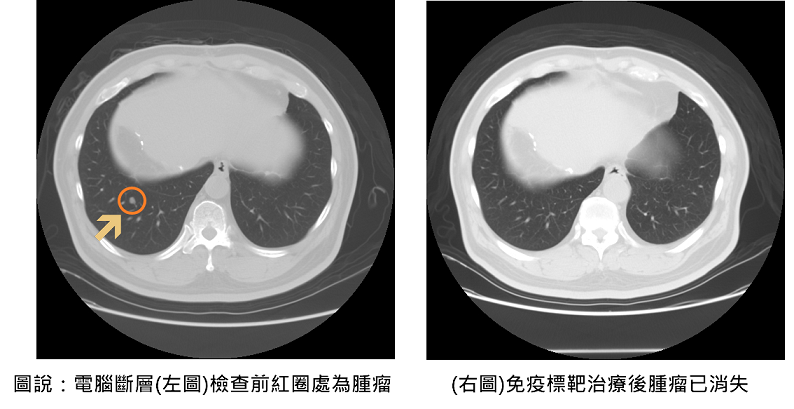

▲電腦斷層治療前後比較。余醫師指出,過去中晚期肝癌的治療主要依賴單一標靶口服藥物,療效有限;而隨著免疫標靶聯合治療的發展,病患的整體存活期已顯著延長至近20個月,死亡風險亦降低約三成。值得注意的是,約10%以下的患者有機會成功治癒,讓腫瘤完全消失,這是以往中晚期肝癌不容易達到的效果。

隨著2023年免疫標靶治療納入健保給付,大幅降低患者經濟負擔,也讓更多中晚期癌友得以接受有效治療。聯新國際醫院腸胃肝膽科余青殷醫師分享一位六十五歲患者,於兩年前接受肝癌切除手術,在術後例行追蹤時,發現甲型胎兒蛋白指數(AFP)持續飆高,以及肺部出現轉移的現象,經評估自體免疫狀況後,醫療團隊決定使用免疫標靶治療,採用第一線免疫標靶聯合療法—免疫藥物「癌自禦」與標靶藥物「癌思停」合併治療,三個月後AFP指數恢復正常,癌細胞亦完全消失,患者未出現任何不適或併發症,生活品質如常。